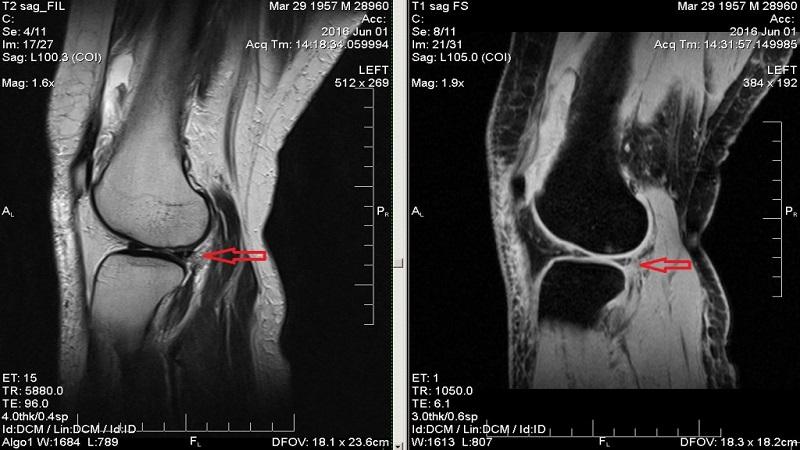

- Томография. Для исследования крупных суставов (коленных, плечевых, тазобедренных) на более ранних стадиях используют КТ и МРТ, так как на них визуализируется более объемное и подробное изображение, чем на рентгене.